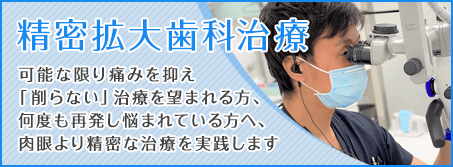

また、昨今、日進月歩の医療技術発展に遅れることなく、いかなる症例ケースでも対応できるように、常に自己研鑽を怠りません。

歯科治療における、充分な知識とそれを裏付ける臨床経験が、大崎オーバルコート歯科・矯正歯科室にはあります。